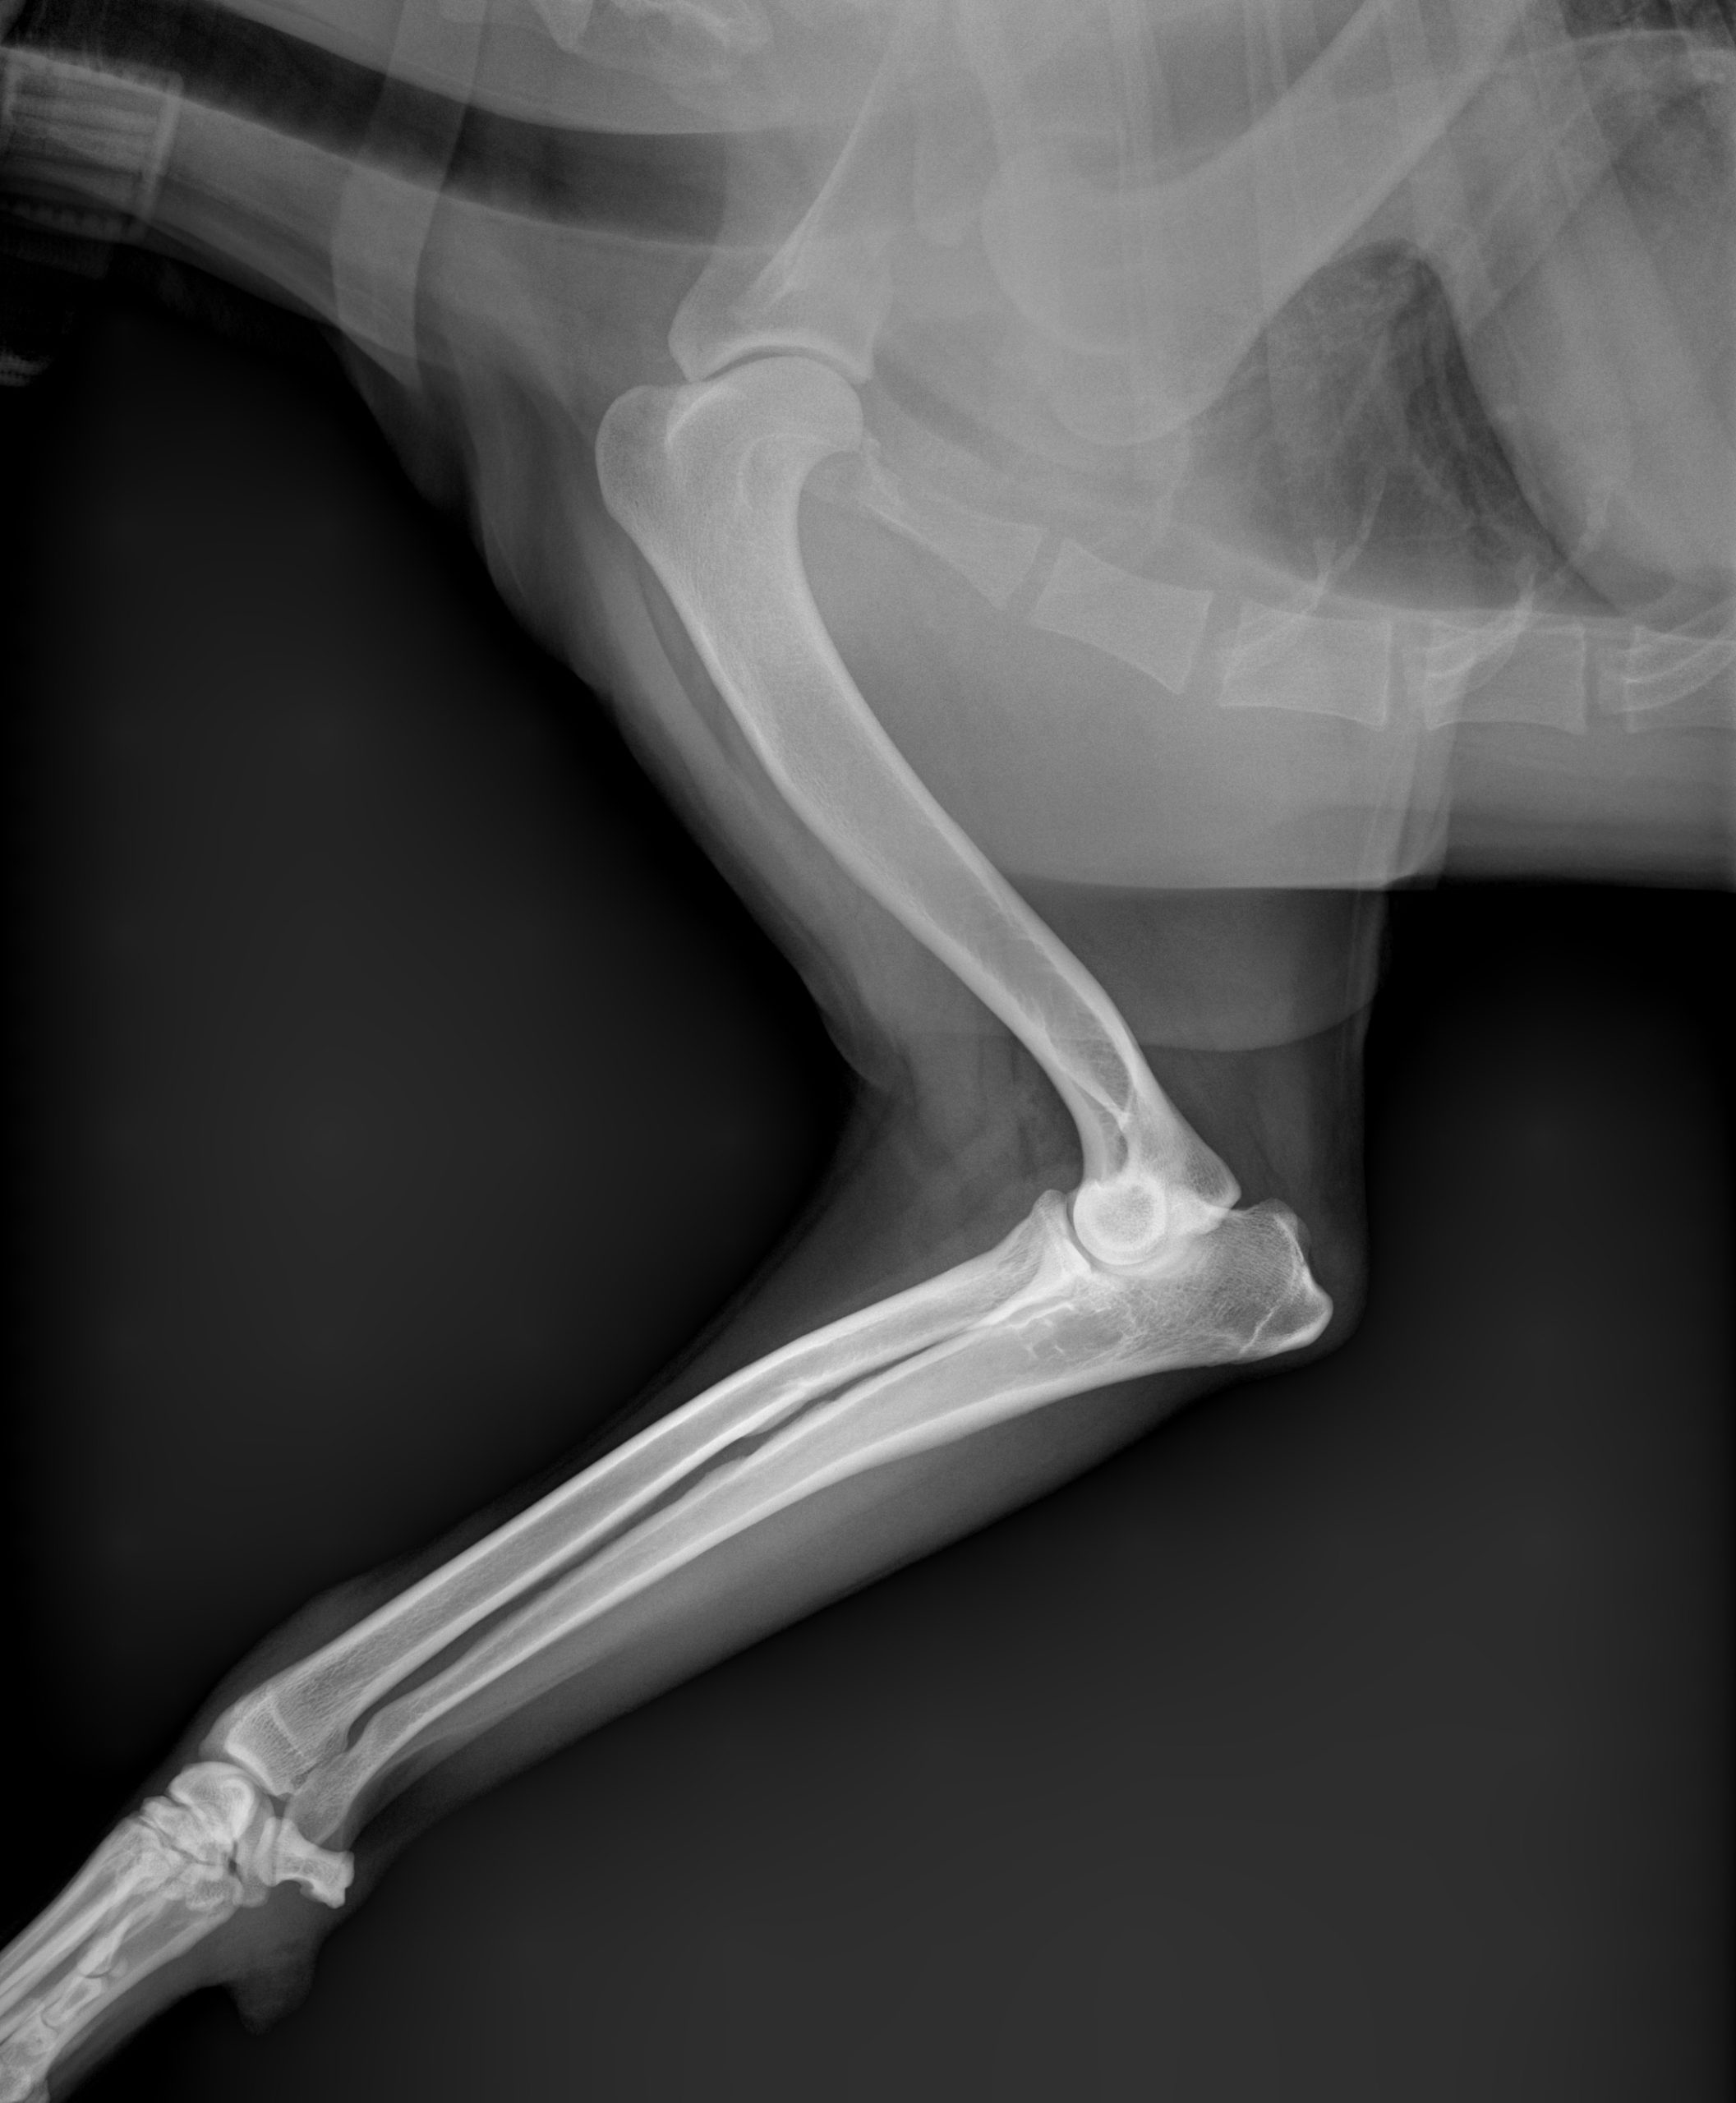

When your pet is hurting, every minute counts. At Veterinary Way Animal Hospital, we utilize top-of-the-line digital radiology equipment to capture high-resolution images of your pet’s internal structures in seconds.

Digital X-rays are a cornerstone of our diagnostic process, allowing our specialty-trained team to perform thorough, in-house evaluations. Compared to traditional film X-rays, digital technology provides clearer images, less radiation exposure for your pet, and the ability to enhance and zoom in on specific areas for a more accurate diagnosis.

- Bone & Joint Health: Identifying fractures, dislocations, and signs of arthritis or hip dysplasia.